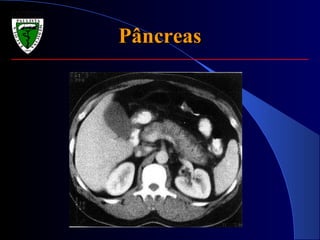

PâncreasPâncreas

 Propedêutica limitadíssima;Propedêutica limitadíssima;

 Sinal de Grey-Turner e Sinal de CullenSinal de Grey-Turner e Sinal de Cullen